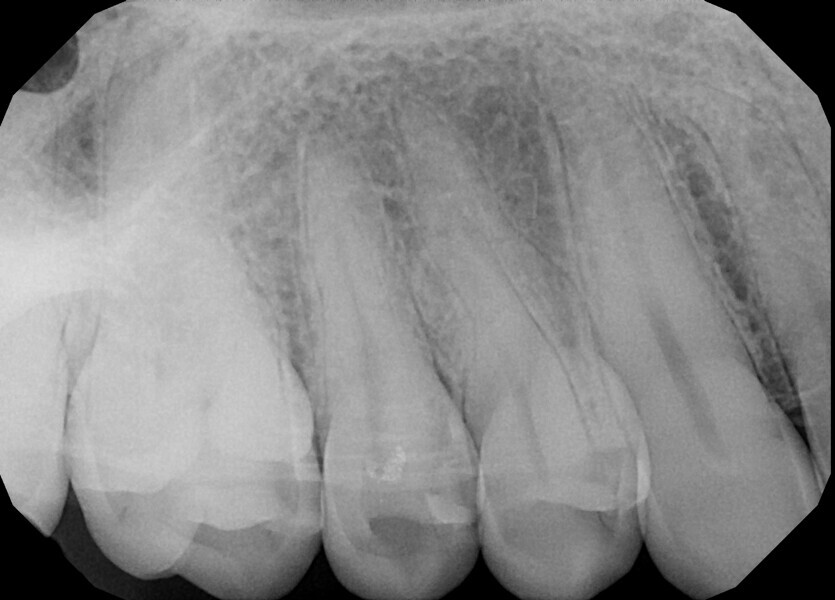

The patient was referred to Dr Witkowski’s dental office for endodontic treatment of teeth #31 and 41 (Fig. 2). After examination, endodontic treatment was performed (Fig. 3). In tooth #41, the access cavity was done by the referring dentist (Fig. 4a). In tooth #31, the access cavity was designed and performed (Fig. 4b). After this step, preparation of the canal space was done, in tooth #41 up to 25/0.04 and in tooth #31 up to 20/0.04 with VDW.ROTATE (VDW; Fig. 5). The next step was the irrigation protocol, which was performed with an Er,Cr:YSGG laser (BIOLASE) at 1.5 W and 100 Hz in both teeth. The canals were prepared for obturation. In tooth #41, obturation was done with a single point and CSBS, and in tooth #31, the piston technique was performed (Fig. 6). A control radiograph was taken immediately after the treatment (Fig. 7). Healing of the lesion was visible on the follow-up radiograph performed six months after the treatment (Fig. 8).

Fig. 8.